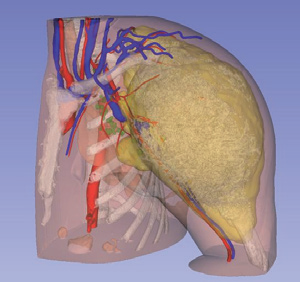

阿梵D——全息医疗影像 三维重建与分析处理系统

术前精准诊断:全面评估病灶影像学特征,直观展示解剖空间结构,帮助完善术前诊断与规划

术中精准定位:准确识别毗邻组织与病灶相对位置,精确测量显示解剖边界,辅助勾画手术切缘

术后快速康复:缩短手术时间,降低手术风险,减轻手术创伤,保留更多肺组织,提升术后生活质量